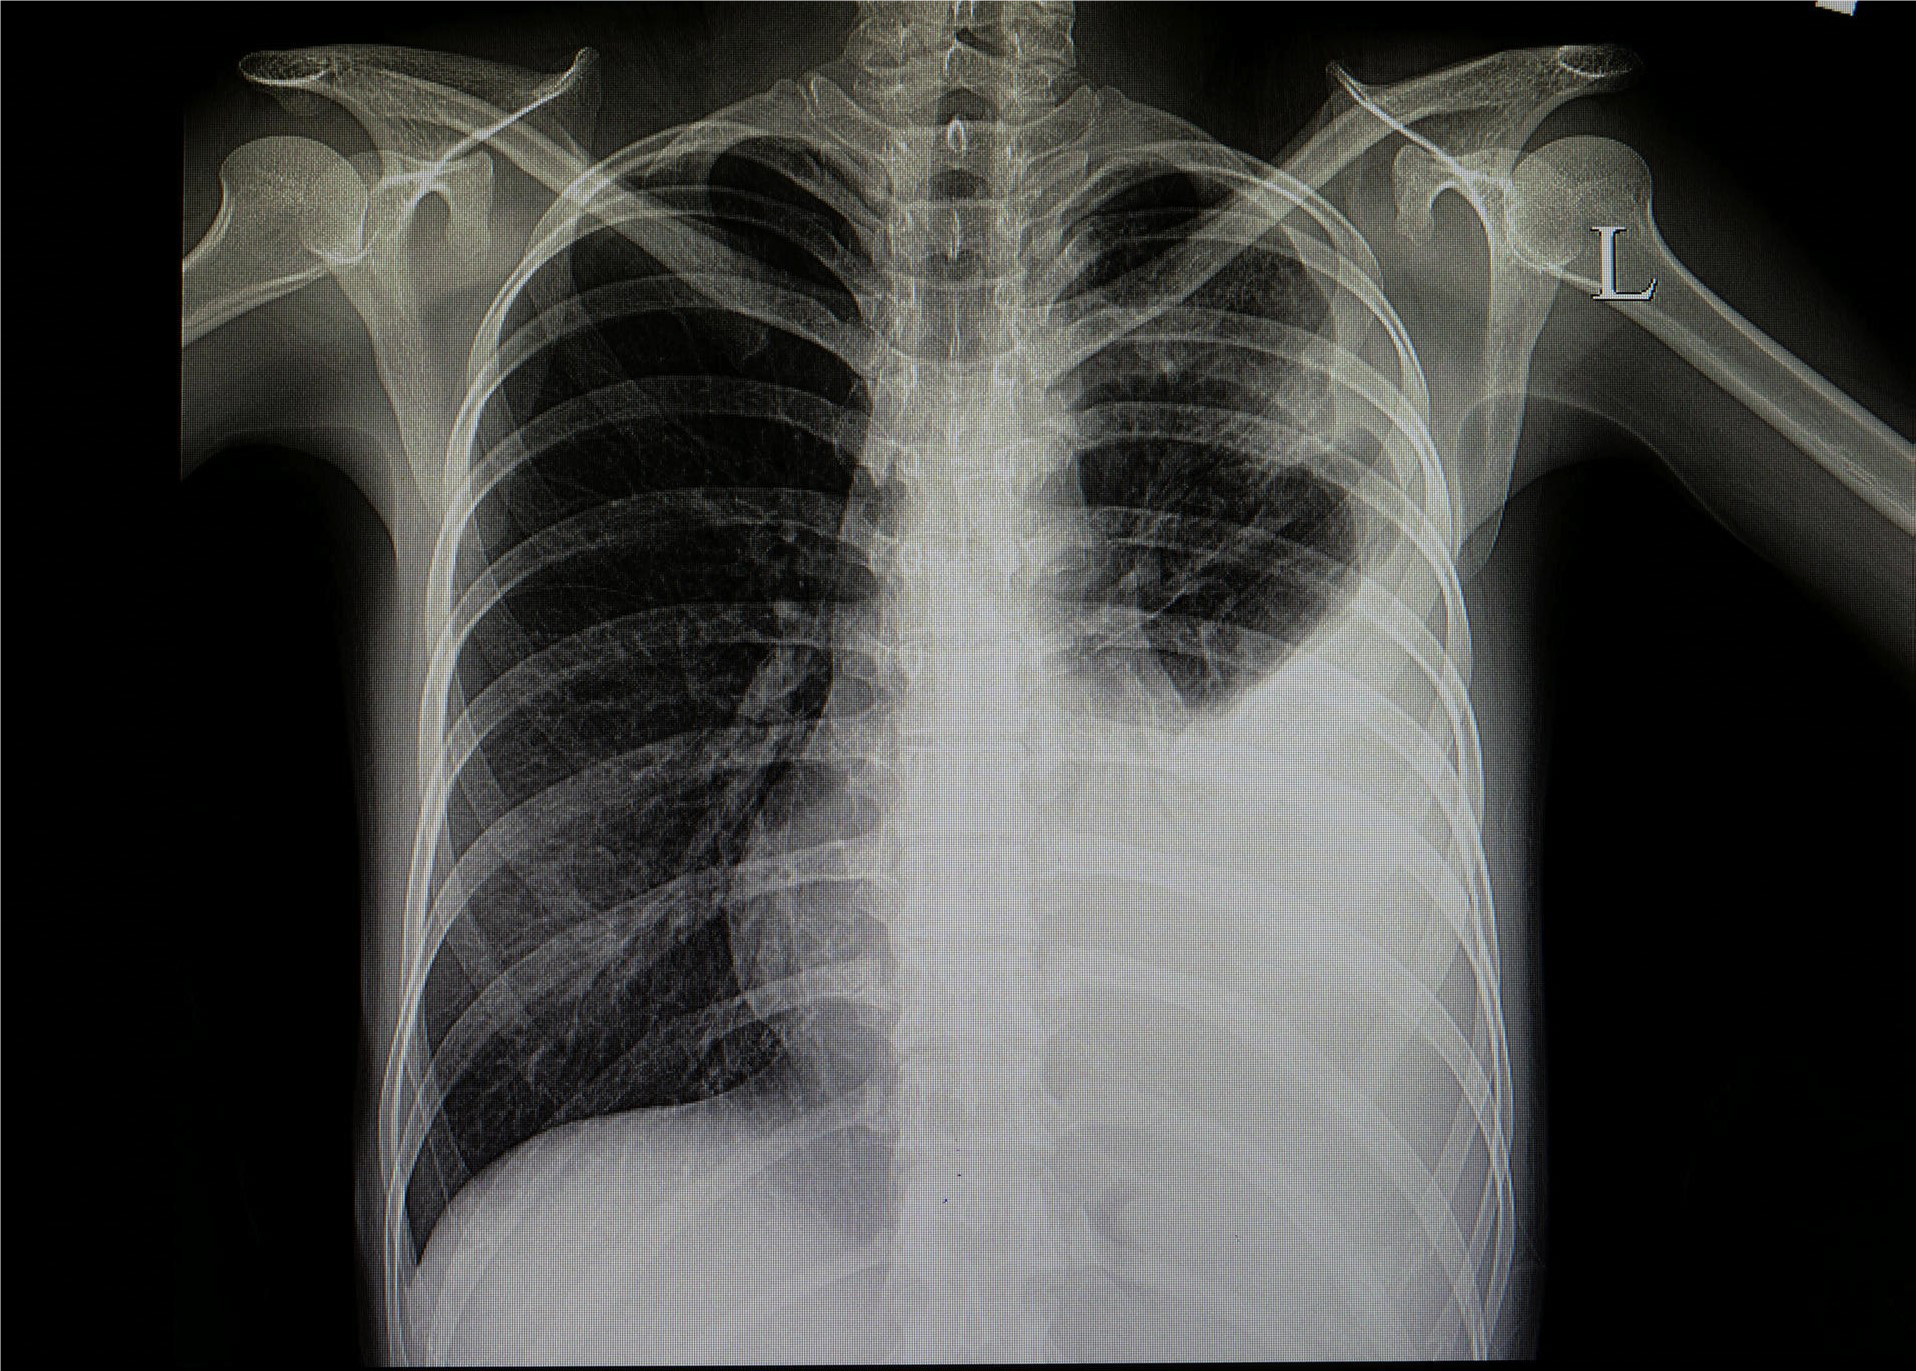

Prof. Dr. Alexander Jesser, betreute gemeinsam mit seinem Mitarbeiter Roman Radtke die Studentin bei ihrer vielversprechenden Forschungsarbeit. Prof. Dr. Jesser erläutert: „Bei einer Erkrankung der Lunge ist das betroffene Gewebe meist weniger transparent für die Röntgenstrahlung und kann durch seine Form und Abgrenzung Aufschluss geben, um welche Art der Krankheit es sich handelt. Eine Covid-19-Erkrankung zeigt meist milchglasartige Veränderungen in beiden Lungenflügeln. Ist eine Erkrankung der Lunge durch eine Infektion mit Bakterien erfolgt, ist mehrheitlich nur ein Flügel der Lunge verändert. Eine gleichmäßige Ausbreitung über alle Bereiche der Lunge ist dabei also ein Hinweis auf eine Covid-19 Infektion.“

Zur automatisierten Auswertung werden die Aufnahmen in einen Standard-PC eingelesen und mit einer speziellen mathematischen Operation der Kontrast erhöht - ein Vorteil bei qualitativ schlechten Aufnahmen, die mit älteren Röntgenanlagen entstehen. Die Software erstellt neben einem Falschfarbenbild, das die Auswertung vereinfachen kann, ein Binärbild, auf welchem sich bereits die Umrisse der Lunge, sowie Spuren von geschädigtem Gewebe erkennen lassen. Durch einen weiteren Algorithmus werden die im Binärbild vorhandenen Kanten und Grenzen der einzelnen Bereiche ermittelt. Die Software kann durch weitere Berechnungen Flächen- und Symmetriebetrachtungen vollziehen und anhand dieser mit großer Wahrscheinlichkeit zwischen bakterieller- oder viraler Lungenentzündungen unterscheiden.